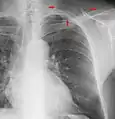

Pleural abnormalities

Fluid in space between the lung and the chest wall is termed a pleural effusion. There needs to be at least 75 mL of pleural fluid in order to blunt the costophrenic angle on the lateral chest radiograph and 200 mL of pleural fluid in order to blunt the costophrenic angle on the posteroanterior chest radiograph. On a lateral decubitus, amounts as small as 50ml of fluid are possible. Pleural effusions typically have a meniscus visible on an erect chest radiograph, but loculated effusions (as occur with an empyema) may have a lenticular shape (the fluid making an obtuse angle with the chest wall).

Pleural thickening may cause blunting of the costophrenic angle, but is distinguished from pleural fluid by the fact that it occurs as a linear shadow ascending vertically and clinging to the ribs.